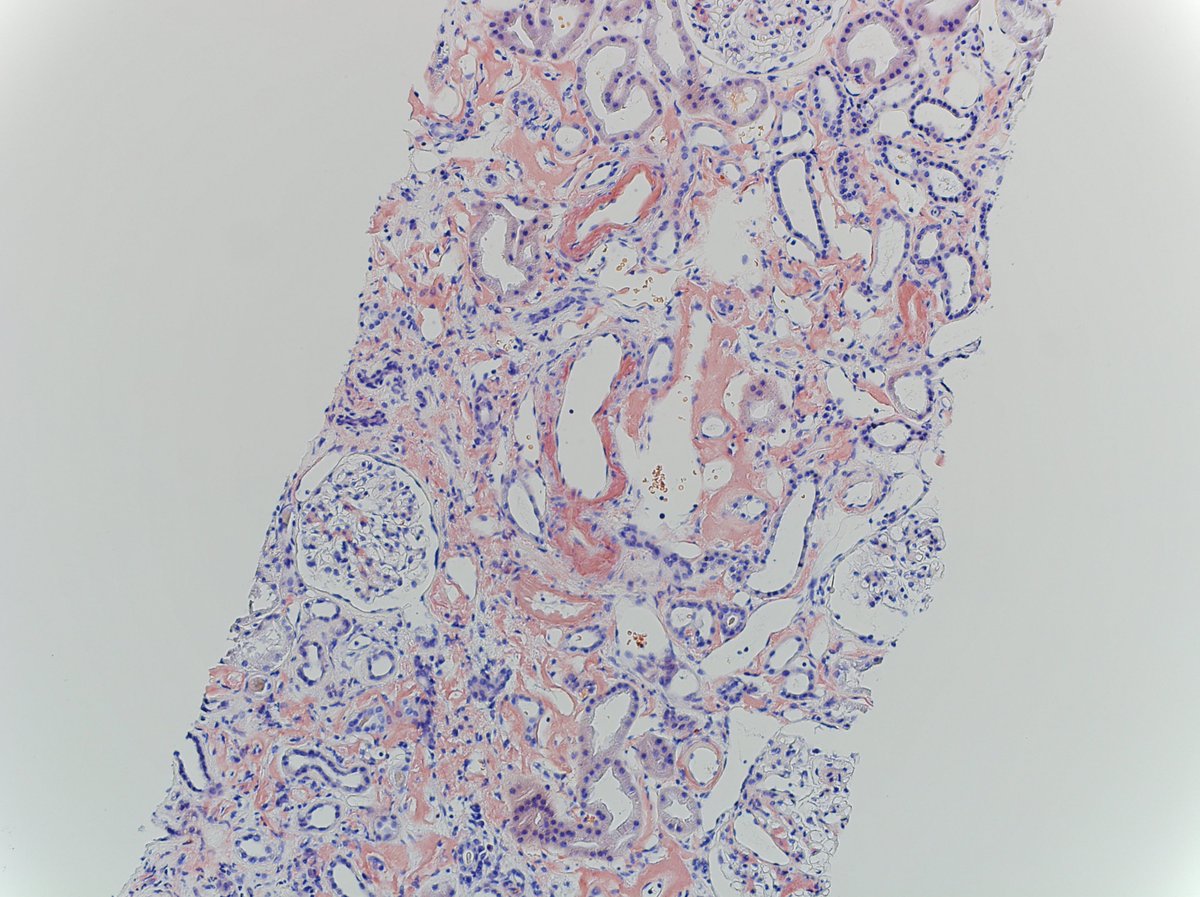

71 yo fem w/ remote hx of breast ca, now w/ enlarged axillary LN. Bx shows tumor cells w/ abundant foamy, pale, eosinophilic cytoplasm, indistinct cell borders, and mild atypia. CK7(+), GATA3(+), e-cad(-)

DX: metastatic lobular carcinoma, histiocytoid variant